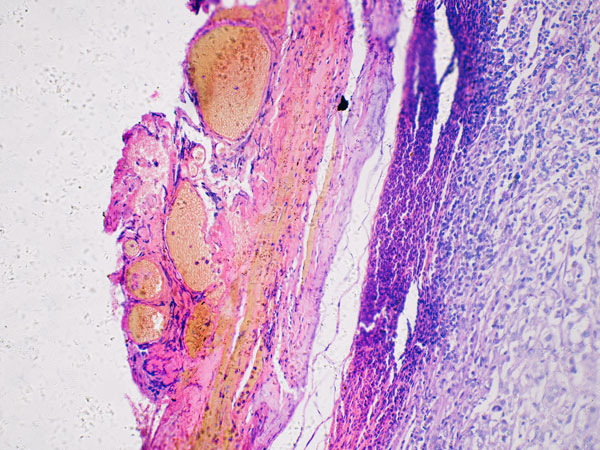

If the dermatologist suspects that the area in question may be cancerous, they may remove part or all of the area and send it to a laboratory for evaluation. This is called a biopsy. A skin biopsy is the only way to know whether the area in question is cancer.20

The dermatopathologist generally shares their findings in a pathology report. If the dermatopathologist finds melanoma, the pathology report will include additional details, such as:20

- How deeply the melanoma has infiltrated the skin

- Excision: A dermatologist tries to remove the melanoma, along with a small border of healthy skin around the area. This extra step may remove additional nearby cancer cells. When the laboratory receives the tissue sample, a specialist, usually a dermatopathologist, examines it under the microscope to search for cancer cells in the border of healthy skin. If no cancer cells appear, the patient may not need further treatment. If some cancerous cells remain, the patient may need additional treatments.20